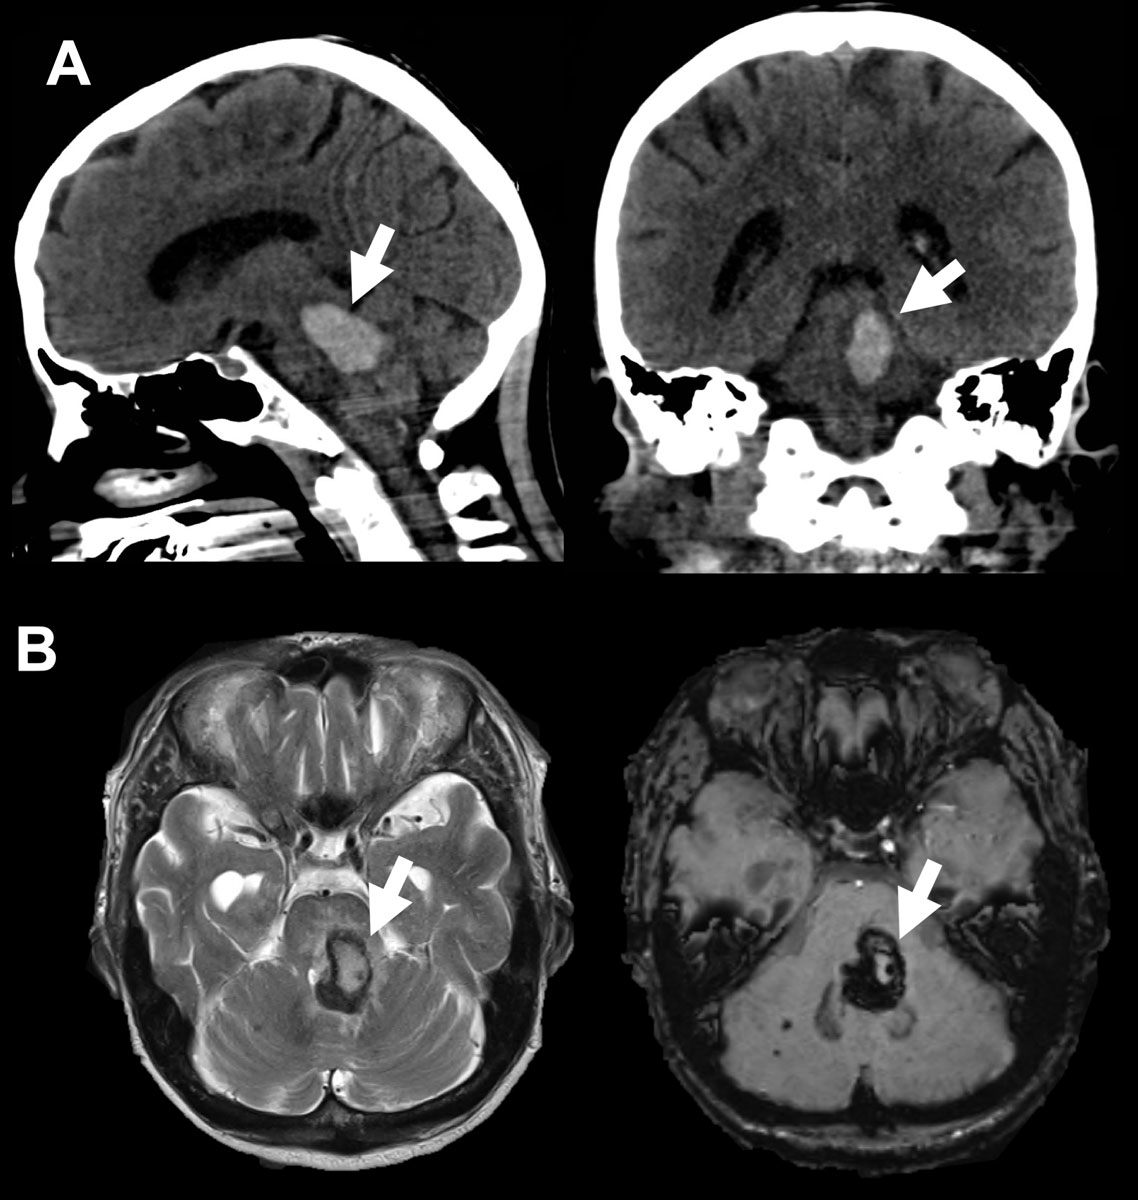

There is a lack of clear brainstem haematoma management recommendations regarding when to consider the termination of treatment due to poor prognosis. These decisions can be quite challenging because brainstem haemorrhage patients are often younger than other ICH patients [4]. In our experience, this decision-making requires not only a close overview of a patient’s concomitant disease, radiological findings, initial neurological symptoms and course after treatment, but also the patient’s presumed will and (most often) cultural factors (fig. 6 presents an illustrative case).

Figure 6 A 66-year-old female patient with Down syndrome presented with fluctuating GCS between 7 and 10 and a “unilateral tegmental” brainstem haemorrhage. Neurological status was no pupil abnormalities and positive left Babinski. Due to neurological deterioration, the patient was intubated right after admission and transferred to the Neurosurgical ICU. Radiologically, no source of bleeding (e.g. vascular malformation) was identified. The patient suffered from known hypertension. Follow-up CT on day +1 showed 5 mm of growth in the haematoma with progressive compression of the fourth ventricle and an enlargement of the ventricular space. An external ventricular drain (EVD) procedure was performed the same day. BAEPs and EEG on day +5 were without pathological findings. After removal of the EVD, the patient again deteriorated neurologically. In conclusion with the radiological findings, a VP-shunt would have been needed long-term. With the perspective of a persistent, severely disabled state of the patient, and taking into account the presumed will of the patient, the family opted for comfort-care, which was initiated on day +18. The patient died on day +19. A. shows a sagittal view and an axial view of the initial CT scan. B shows the initial MRI scan and the extent of the haemorrhage (FLAIR left and SWI right). The Arrow (→) indicates the haemorrhage.